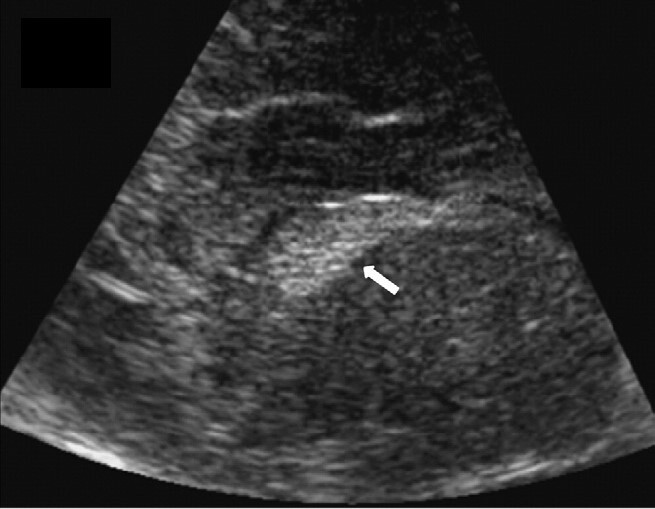

Neonatology Non-hemorrhagic Germinal Matrix Image